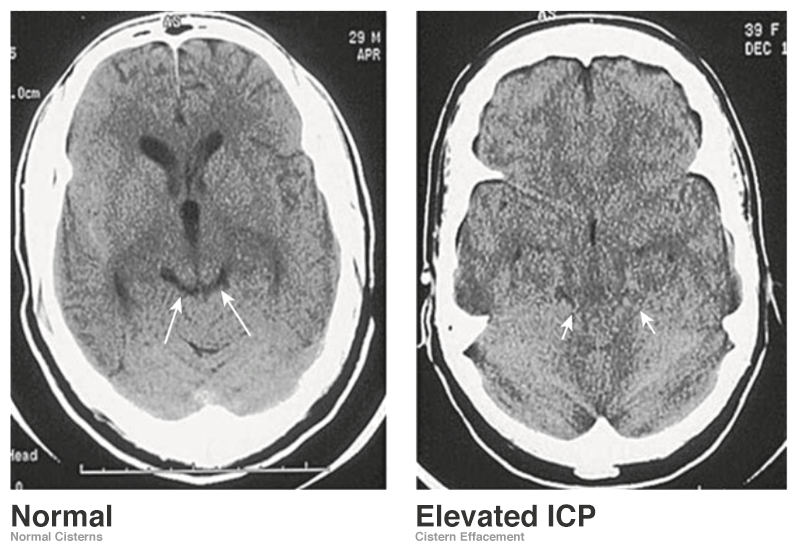

Intracranial Hypertension Ct Brain Signs Radiology Signs are useful in radiology since they are easy to remember, can help recognize presence of abnormalities, and narrow the list of. The prominent vessel sign, or prominent hypointense vessel sign, is a radiological sign appreciated on susceptibility. In this study, we demonstrate some of the more common and useful neuroradiologic signs with relevant images, and discuss their use in.. Brain Signs Radiology.